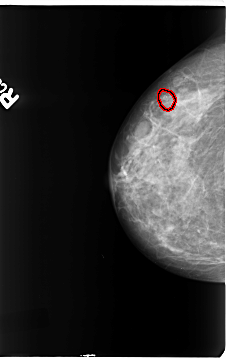

B_3145_1.RIGHT_MLO

RIGHT_CC LINES 4664 PIXELS_PER_LINE 2936 BITS_PER_PIXEL 12 RESOLUTION 50 OVERLAY

FILE: B_3145_1.RIGHT_CC.OVERLAY

TOTAL_ABNORMALITIES 1

ABNORMALITY 1

LESION_TYPE CALCIFICATION TYPE PLEOMORPHIC DISTRIBUTION CLUSTERED

ASSESSMENT 4

SUBTLETY 4

PATHOLOGY BENIGN

TOTAL_OUTLINES 1

BOUNDARY